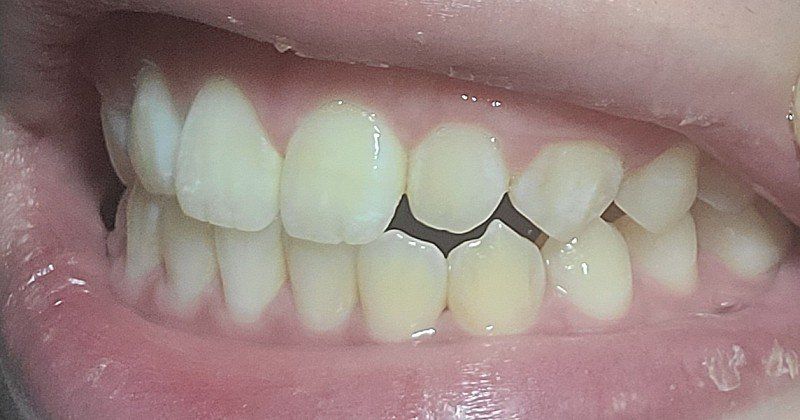

두번째 앞니사진

정면사진

억지로 중심선 맞춘사진1

억지로 중심선 맞춘사진2

억지로 중심선 맞춘사진3